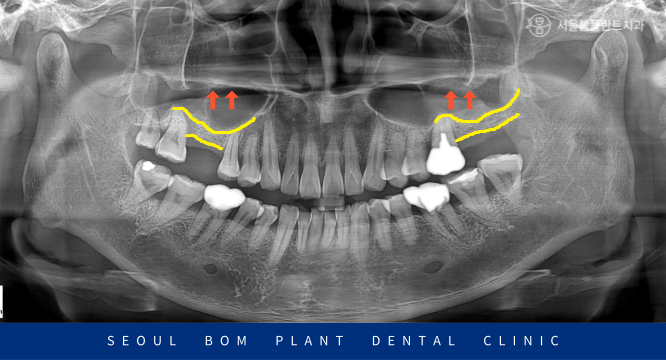

그런데 환자분의 경우

남아 있는 뼈의 양이 적고,

상악동이 많이 내려와 있는

상황이었습니다.

이 경우 내려와 있는 상악동을 올리고

뼈이식을 진행한 뒤

임플란트 식립을 하는

‘상악동 거상술’을 동반한

임플란트 식립이 필요했습니다.

환자분의 경우 잔존 뼈의 두께가

3mm 이하였기 때문에

측방 접근법을 이용한

상악동 거상술을 동반하여 뼈이식 후

임플란트 식립을 진행해 드렸습니다.